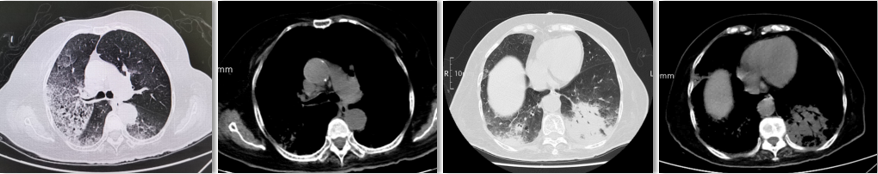

为提升肺癌前线免疫联合抗血管治疗的诊疗观念,学习与追踪肺癌领域诊疗最前沿知识,充分交流免疫/抗血管用药不良反应管理临床经验,【An例说】肺癌病例项目,征集大量临床高质量免疫联合抗血管治疗肺癌病例,并邀请全国各区域中青年及高职称医生与顶级TOP KOL互动发声!通过理念结合实践,研究结合病例,线上联动,共同促进学术由KOL/ROL向中青年医生下沉,为提升我国肺癌诊疗整体水平势在必行。免疫治疗的出现,对于晚期肺癌患者而言,显著提高了患者的生存质量及延长生存期,多项研究表明免疫治疗对于PD-L1表达阴性的患者也具有一定的治疗效果。为此,上海长海医院(海军军医大学第一附属医院)团队为您带来一例肺癌免疫联合抗血管病例分享。 患者,女性,78岁 2017年体检时发现左下肺结节,未行诊断及治疗。 2018.11.21、2019.09.24胸部CT均提示病灶较前变大,仍未诊治。 影像学检查 2020.01初逐渐出现胸闷、气短,活动后尤为明显。多次就诊于当地医院输液治疗(具体不详)。入院前2周胸闷,气急症状加重,无发热,无明显咳嗽,咳痰。2020.06.23入院。 影像学检查 既往史:高血压病30余年,最高血压170/90mmHg,规律服用美托洛尔12.5mg+利血平 0.1mg/日,自诉血压控制可。 个人史:无特殊 婚育史:无特殊 家族史:无特殊 T:37.0℃ P:104次/分 R:30次/分 BP:134/58mmHg 右肺及左肺可闻及湿罗音,左下肺呼吸音弱,无胸膜摩擦音。 心脏查体无异常。 入院后 CT引导下肺穿刺 穿刺后无咳嗽咯血,胸闷气急症状无加重。 6.25 出院等病理。 自行口服易瑞沙治疗,家中持续吸氧。 出院后3天突发病情变化: 6.28 凌晨1点左右,如厕后出现呼吸困难加重,晕倒。家属约2点发现,送至急诊,急诊予化痰、平喘、抗感染等对症治疗。 影像学检查 急诊检验检查: 【血气分析】PH 7.35、PO2 45.9mmHg、PCO2 62.6mmHg 【BNP】23.38pg/ml;【D-二聚体】0.32 【血常规】WBC:9.23×109/L、RBC:3.58×1012/L、HGB:98g/L、N%:80.2%、PLT:203×109/L。 【炎症指标】CRP:2.95mg/L;ESR:4mm/H;PCT:0.045ng/ml 【心电图】1. 窦性心动过速、2. ST-T异常。 血气分析 2020.06.29再次入院:左下肺腺癌、Ⅱ型呼吸衰竭、右肺阴影待查。 右肺渗出原因分析:感染?肿瘤进展?药物相关? 血常规变化: 选择治疗方案: 1. 两肺炎症,纵隔稍大淋巴结,炎症较2020.6.24进展,建议抗炎治疗后复查; 2. 左侧胸腔少许积液; 3. 两肺肺气肿、肺大泡,右肺中叶钙化灶; 4. 右侧第4肋骨皮质扭曲,请结合临床; 5. 甲状腺两侧结节,请结合超声。 右下肺腺癌 PD-L1无表达 抗血管生成与免疫联合的优点: 1、抗血管生成,靶点全面、强效抑制 2、抑制肿瘤细胞增殖和迁移,重塑肿瘤微环境,联合增效 3、肿瘤血管正常化及重塑,减轻免疫抑制状态 4、增加免疫效应细胞浸润 5、免疫刺激作用,激活免疫效应细胞 信迪利单抗联合安罗替尼的临床研究:这是一项前瞻性、非随机、三臂、Ib期临床研究。 临床研究试验设计 临床研究PFS和OS曲线 安罗替尼联合信迪利单抗一线治疗NSCLC,ORR达72.7%,DCR达100%,mPFS=15.6m,24m,OS率83.9%,表现出良好的治疗潜力。 派安普利单抗联合安罗替尼的临床研究:随机、双盲、多中心III期临床研究(NCT03866980) 临床研究试验设计 安尼可联合安罗疗效的ORR和DCR分析 数据截止日期:2021.1.13,共26例患者入组安尼可联合安罗替尼组,21例患者至少完成一次疗效评价。 帕博利珠单抗+安罗替尼 8mg。 治疗过程影像学检查 疗效评估: 2021.08.03: 疗效评估PR,截止目前PFS=15m。 该病例采用PD-L1抑制剂帕博利珠单抗联合小分子多靶点抗血管生成药物安罗替尼治疗老年肺腺癌患者,获得了15个月的PFS,提示对于驱动基因阴性,PD-L1无表达的晚期非小细胞肺癌患者免疫联合抗血管生成药物治疗是NSCLC患者一线治疗的选择和手段之一。 Impower150研究显示,贝伐珠单抗联合PD-L1抑制剂阿替利珠单抗+化疗显著改善了无突变非鳞NSCLC患者的PFS,中位OS达19.4个月(对照组14.7个月),ORR为71%。但治疗相关的毒副反应较大,一定程度上影响患者生活质量。小分子TKI联合免疫作为肿瘤去化疗联合治疗模式,越来越受到关注,前期探索性前瞻性随机临床研究包括信迪利单抗+安罗替尼(ACTION研究)、派安普利单抗+安罗替尼(AK105-301研究)和卡瑞利珠单抗+Apatinib/ target=_blank class=infotextkey>阿帕替尼(SHR-1210-III-315 研究)等一线治疗驱动基因阴性晚期NSCLC均得到了较好结果, 信迪利单抗联合安罗替尼组ORR达72%,DCR100%,中位PFS15.6个月,2年OS率83.9%,耐受性良好,显示出多靶点抗血管生成药物联合的良好应用前景。 免疫与抗血管生成药物以及与其他药物或方式联合该如何排兵布阵,肺癌治疗如何真正践行个体化和精准化,还有许多问题和挑战,有待进一步研究拓展和证实。 病例分享 焦洋 教授 上海长海医院,副主任医师,副教授 海军军医大学长海医院呼吸与危重症医学科 美国田纳西州大学附属医院呼吸与危重症医学科访问学者 上海市医学会呼吸分会感染学组秘书 中国老年医学会感染诊治与合理用药学术委员会委员 专业方向:疑难、复杂肺部感染及呼吸危重症的救治,肺癌的早期诊断和治疗。 专家点评 韩一平 教授 海军军医大学第一附属医院 呼吸与危重症医学科教授、主任医师 博士生导师 海军军医大学第一附属医院临床教育中心主任 中华医学会呼吸分会肺癌学组委员 中国医药教育协会肺部肿瘤专委会常委 中国医师协会全科分会委员,上海全科分会副会长 《中国肿瘤生物治疗杂志》《中国全科医学杂志》 《第二军医大学学报》《内科年鉴》等编委 获校“特级优秀教师”,上海市“育才奖” 首届上海“最美女医生” 主编发表教材或专著5部,近年发表文论50余篇 *仅供医学药学专业人士阅读 文章来源:ONCO前沿案例详情